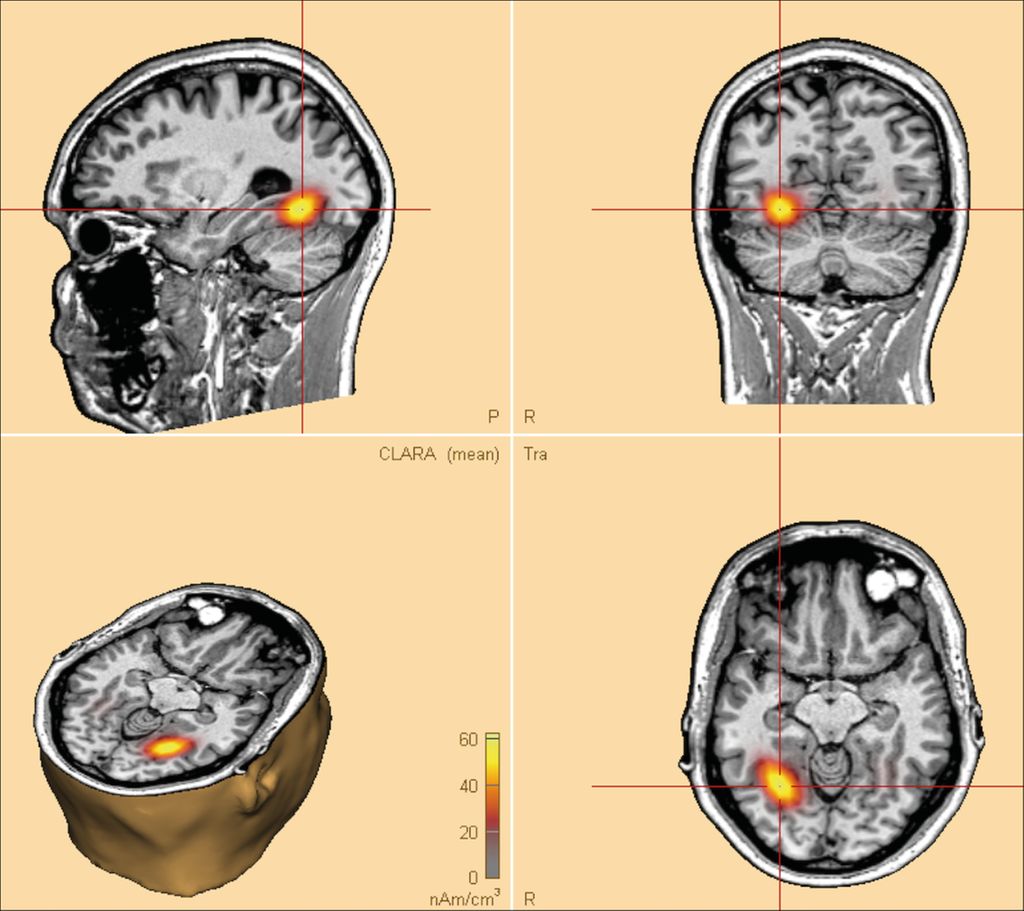

L. Imbach: Generell erst einmal nur die mit fokaler Epilepsie. Es hängt dann noch davon ab, wo der Epilepsieherd ist und ob der Neurochirurg mit dem Eingriff keine oder kaum Defizite in der Hirnfunktion verursachen würde. Um das sagen zu können, sind neben einer detaillierten Anamnese mindestens hochauflösende Hirn-MRT, interiktales EEG, Video-EEG-Dokumentation patiententypischer Anfälle, funktionelle Bildgebung (fMRT, PET) und eine detaillierte neuropsychologische Diagnostik notwendig. Lässt sich der Herd damit nicht exakt lokalisieren, wenden wir auch mathematische Modelle und Methoden der künstlichen Intelligenz an (Abb.1).

Abb. 1: Rekonstruktion von EEG-Daten auf einem Computer-generierten Hirn. Zu erkennen ist der Herd, von dem die Epilepsie ausgeht. Der Computer berechnet anhand der Untersuchungsergebnisse und Daten des Patienten, wie gross die Wahrscheinlichkeit ist, dass der Ausgangspunkt in einem bestimmten Hirnbereich liegt. Das hilft bei der Entscheidung, ob der Patient operiert und dadurch anfallsfrei werden kann